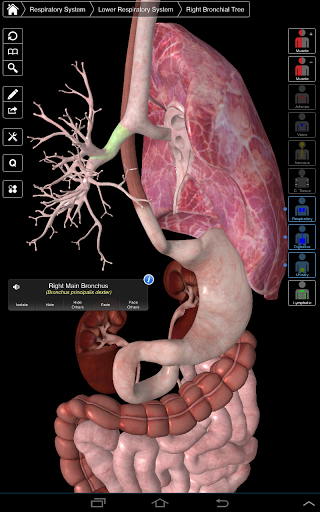

Основна анатомія 3 - це найновіша технологія та новаторський дизайн. Ріжучий 3D-графічний движок, зроблений на замовлення 3D4Medical з усього світу, наділений високоінформативною анатомічною моделлю і забезпечує високу якість графіки, яку не може досягти ніхто інший конкурент.

Програма являє собою унікальний підхід до вивчення загальної анатомії. Графіка не має аналогів і навчається, використовуючи інформативний контент та інноваційні функції, багатий та захоплюючий досвід.

НОВІ 3D-ТЕХНОЛОГІЇ

Основна Анатомія 3 чутлива, візуально приголомшлива і легка. Додаток повністю 3D, що означає, що ви можете переглядати будь-яку анатомічну структуру окремо, а також з будь-якого кута.

---- Більше 4000 дуже детальних анатомічних структур